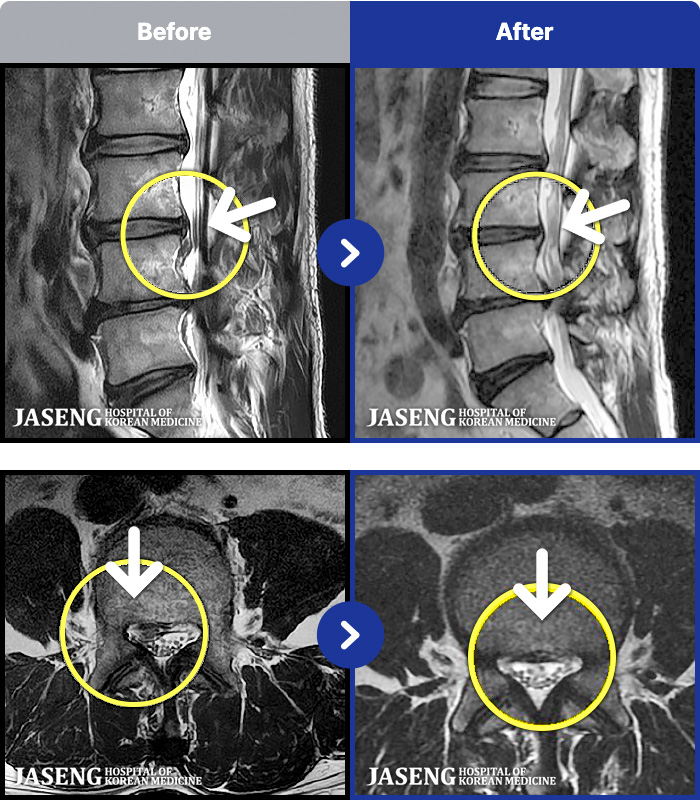

54 MRI ũ ʸ Ȯϼ.

[뱸] 19.11.28~25.05.06